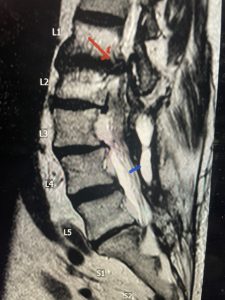

This 66 year-old male with Factor XI deficiency had originally had a decompressive laminectomy L2-S1 and in situ fusion about three years prior for severe thecal sac compression mainly due to severe epidural lipomatosis (Fig 4).

(Fig 4a) Sagittal (a) and Axial (b) T2-weighted lumbar MRI demonstrating severe spinal stenosis L2-5 (arrow)and extruded disc at L3-4 on axial image (arrow)

(Fig 4b)

Epidural lipomatosis is a relatively rare condition where normally present fat in the epidural space is hypertrophied and can cause severe thecal sac compression. It is generally deposited more in the lateral and dorsal epidural space. This can be caused by long term steroid use and obesity, but also can be idiopathic. He had done well until more recently had developed low back pain with bilateral thigh pain and numbness. He had difficulty walking because of the pain. A new MRI (Fig 5) revealed that he had developed severe degeneration of the L1-2 segment above his prior decompression and fusion with a large extruded disc/osteophyte, right greater than left with severe thecal sac compression. He also had some residual T12-L3 residual epidural lipomatosis.